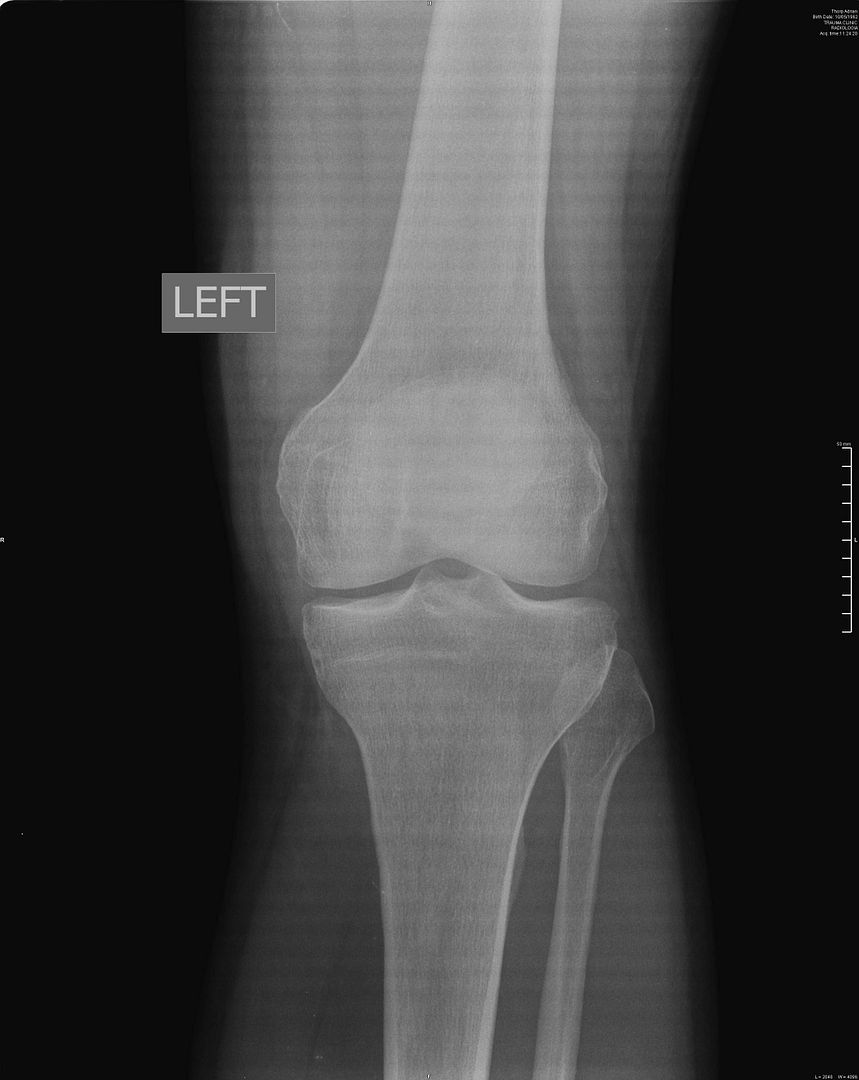

Medial Tibial Plateau Fracture Skiing After Tibial Plateau Fracture But if you do your pt and keep off. fewer than half of skiers who underwent operative fixation of a tibial plateau fracture could return to skiing at a. fewer than half of skiers who underwent operative fixation of a tibial plateau fracture could return to skiing at a. explore the journey back to the slopes after. Skiing After Tibial Plateau Fracture.

Moore type 1 tibial plateau fracture secondary to alpine ski injury Skiing After Tibial Plateau Fracture But if you do your pt and keep off. outlined below is a possible skiing management plan or programme which could be followed by someone. my main point here is that a tibial plateau fracture is serious. fewer than half of skiers who underwent operative fixation of a tibial plateau fracture could return to skiing at a.. Skiing After Tibial Plateau Fracture.

Schatzker Classification of Tibial Plateau Fractures RadioGyan Skiing After Tibial Plateau Fracture outlined below is a possible skiing management plan or programme which could be followed by someone. fewer than half of skiers who underwent operative fixation of a tibial plateau fracture could return to skiing at a. But if you do your pt and keep off. my main point here is that a tibial plateau fracture is serious.. Skiing After Tibial Plateau Fracture.